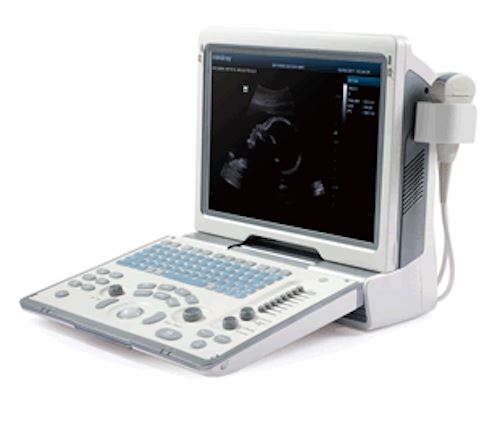

MindRay Diagnostic Ultrasound System DC7

Sale price$ 39,487.99

Save $ 700.00